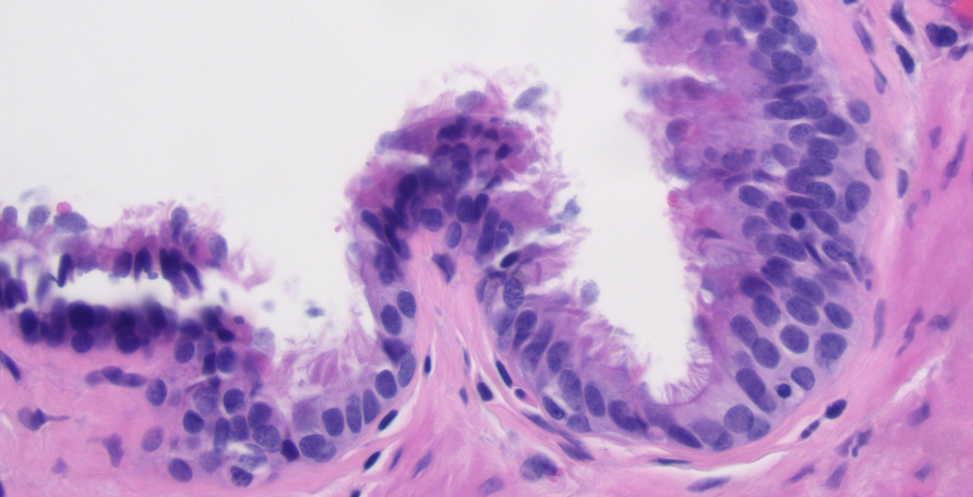

A 28-year-old healthy gentleman with no prior medical history presented to the emergency room with sudden onset of severe right upper quadrant and epigastric abdominal pain associated with nausea and vomiting. Liver enzymes and lipase were normal. CBC showed mild leukocytosis (12.24 K/microL).  Cross-sectional imaging revealed a well-circumscribed soft density lesion adjacent to the gastroesophageal junction (Fig. 1). Ultrasound evaluation did not show any cholecystitis or gall stones. Esophagogastrostomy did not show significant changes in the esophagus or in the gastroesophageal junction or in the stomach. Endoscopic ultrasound evaluation showed a well encapsulated lesion measuring 3 cm not arising from the muscularis propria of the esophagus but close to the GE junction with both liquid and solid contents (Fig. 2). Needle aspiration showed mucinous material suggesting possible esophageal duplication cyst.  Laparoscopy was performed ,revealing a pedunculated  cystic lesion at the gastroesophageal junction (Fig. 3). It was stapled at its origin, with a bougie in the esophagus to minimize the risk of narrowing the esophageal lumen (Fig. 3). Histopathological examination confirmed it was indeed an esophageal duplication cyst (Fig. 4,5 &6). The inner lining of the cyst was ciliated columnar epithelium (Fig. 4). Interestingly double layer of smooth muscle was noted (Fig. 6). Following surgical removal, the pain completely resolved and on follow up the patient was feeling completely normal.

Figure 1. CT scan showing the lesion adjacent to the GE junction

Figure 4. High power view (40 x) of an H&E stained section of the cyst lining demonstrating the ciliated columnar epithelium

Fig. 5. Low Power view (4x) of an H&E stained section of showing cystic structure with a well-developed smooth muscle layer forming the wall and lined by ciliated columnar epithelium. No cartilage identified.